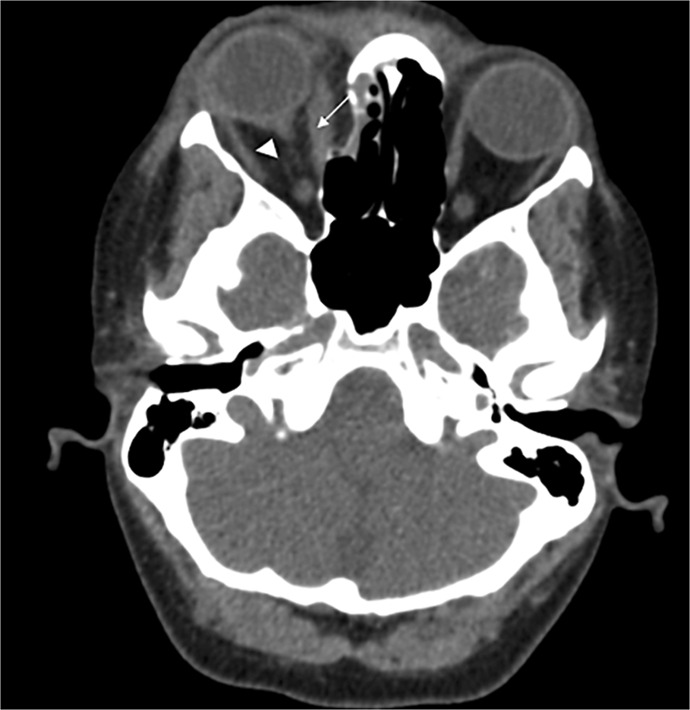

Case report: A 45-year-old woman presented with sudden vision loss in her right eye 3 h after sustaining blunt trauma from a wood fragment while chopping firewood. Initial examination revealed no light perception (NLP) in the affected eye and a relative afferent pupillary defect. Imaging revealed hyperdensity and thickening of the posterior sclera, the intraocular and anterior intraorbital optic nerve. Despite administration of intravenous steroids and a neurosurgical consultation for TON, retinal evaluation 1 day post-trauma revealed retinal edema, pallor, multiple vascular occlusions, and a cherry-red spot, leading to a diagnosis of CRAO associated with TON. Ongoing follow-ups showed persistent NLP in the right eye.